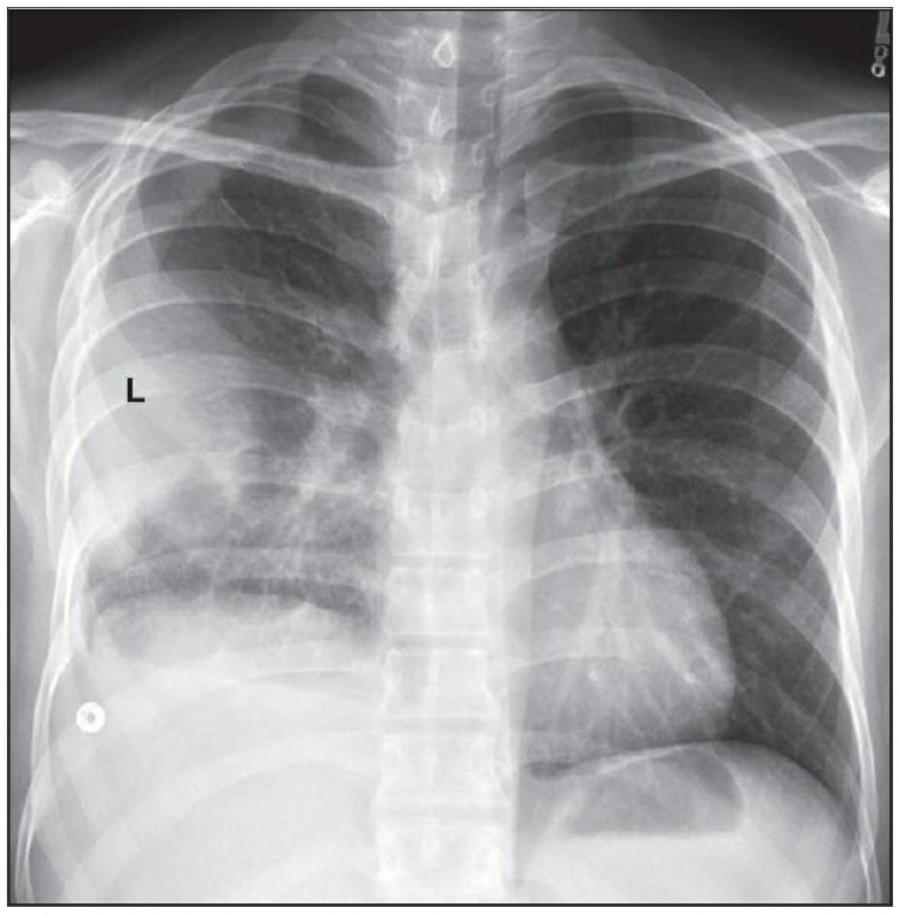

방사선 소견상 Pleural effusion은 환자 흉부의 dependent area에 고인다. Erect position에서 확인하기가 쉬운데, 폐의 base에 고임으로써 costophrenic angle blunting을 보이고 lower lobe vessel들의 흐리게 한다. Supine position에서는 확인이 더 어려운데, pleural fluid는 posterior basilar space에 고여서 폐 base 쪽으로 intensity가 증가하는 homogenous density를 보인다. 정상적인 bronchoalveolar marking은 이와 같은 veil-like density 안에서 확인 가능하다. Fluid 양이 늘어나면서 diaphragm의 윤곽이 흐릿해지고 costophrenic angle도 없어지는데, 이 costophrenic angle blunting이 없더라도 pleural space에 1L 정도의 pleural fluid가 있을 수 있다는 것을 기억해야 한다. 그 양이 더욱 늘어날 수록 fluid는 lung의 apex에서 pleural cap으로 나타날 수 있으며, 이는 supine position에서도 확인 가능하다. Pleural fluid는 lung의 medial side에 고일 수도 있으며 이는 mediastinum의 확장으로 보일 수도 있다.

적은 양의 pleural fluid는 꼼꼼히 확인하더라도 supine radiograph에서 놓칠 수 있는데, 만약 chest X ray에서 보이지 않지만 임상적으로 의심이 되는 경우에는 lateral decubitus film으로 확인해 볼 수 있다. Fluid는 dependent position에 고이므로 환자를 의심되는 방향으로 옆으로 눕혀야 한다. Lateral decubitus film은 적은 양의 pleural fluiid는 물론이고 loculated effusion과 free effusion을 확진하는 데도 도움이 된다. 특히 loculated effusion은 한 개 이상의 drain이 필요할 수 있으므로 pleural drainage를 고려할 때 특히 중요한 검사이다. 중환자에서 흔하게 나타나는 subplumonic effusion은 lung base에 존재하는 pleural effusion을 말하는데, chest X ray 상에서 raised hemidiaphragm with flattening and lateral displacement of the dome 형태로 나타나며, lateral decubitus film이 도움이 된다.